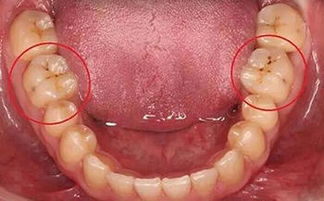

2、定期復(fù)查:對(duì)于牙髓炎,根尖周炎的患者根管治療后,建議遵照醫(yī)囑,每3個(gè)月或6個(gè)月到醫(yī)院定期復(fù)查,拍牙片隨訪牙齒內(nèi)部情況。

3、佩戴保護(hù)措施:如牙冠、嵌體,根管治療后患者牙齒較脆,易裂,建議佩戴保護(hù)措施,避免牙齒裂開。若患牙裂開,在目前的醫(yī)療技術(shù)下,只能選擇拔除患牙。